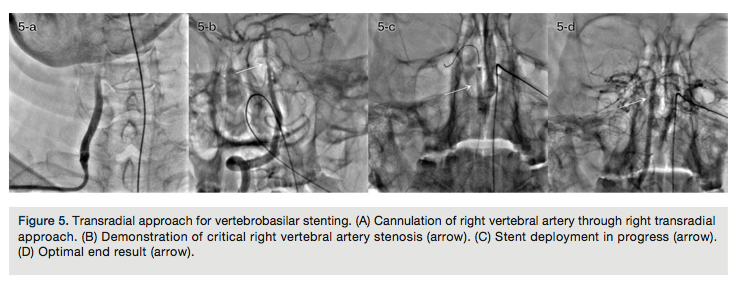

TRA for vertebrobasilar stenting. Endovascular intervention of vertebrobasilar stenosis is a relatively new alternative modality of management, supported by very few case reports and studies.13,50 TFA has been the preferred approach in most studies. However, a recent study has documented the feasibility and reproducibility of the TRA in chronic as well as acute occlusions of the vertebrobasilar system.13

A 6Fr internal memory artery guide catheter through ipsilateral TRA easily cannulates the vertebral artery ostium. The same guide catheter with side-holes should be used to address ostial vertebral artery stenosis (Figures 5A and 5B).

-

Regular PTCA guidewires, balloon catheters, and coronary stents should be used (Figures 5C and 5D).

Predilation of the lesion should be done with low pressure (between 4 and 6atm).

The stent should be deployed at low pressure (8-10atm).